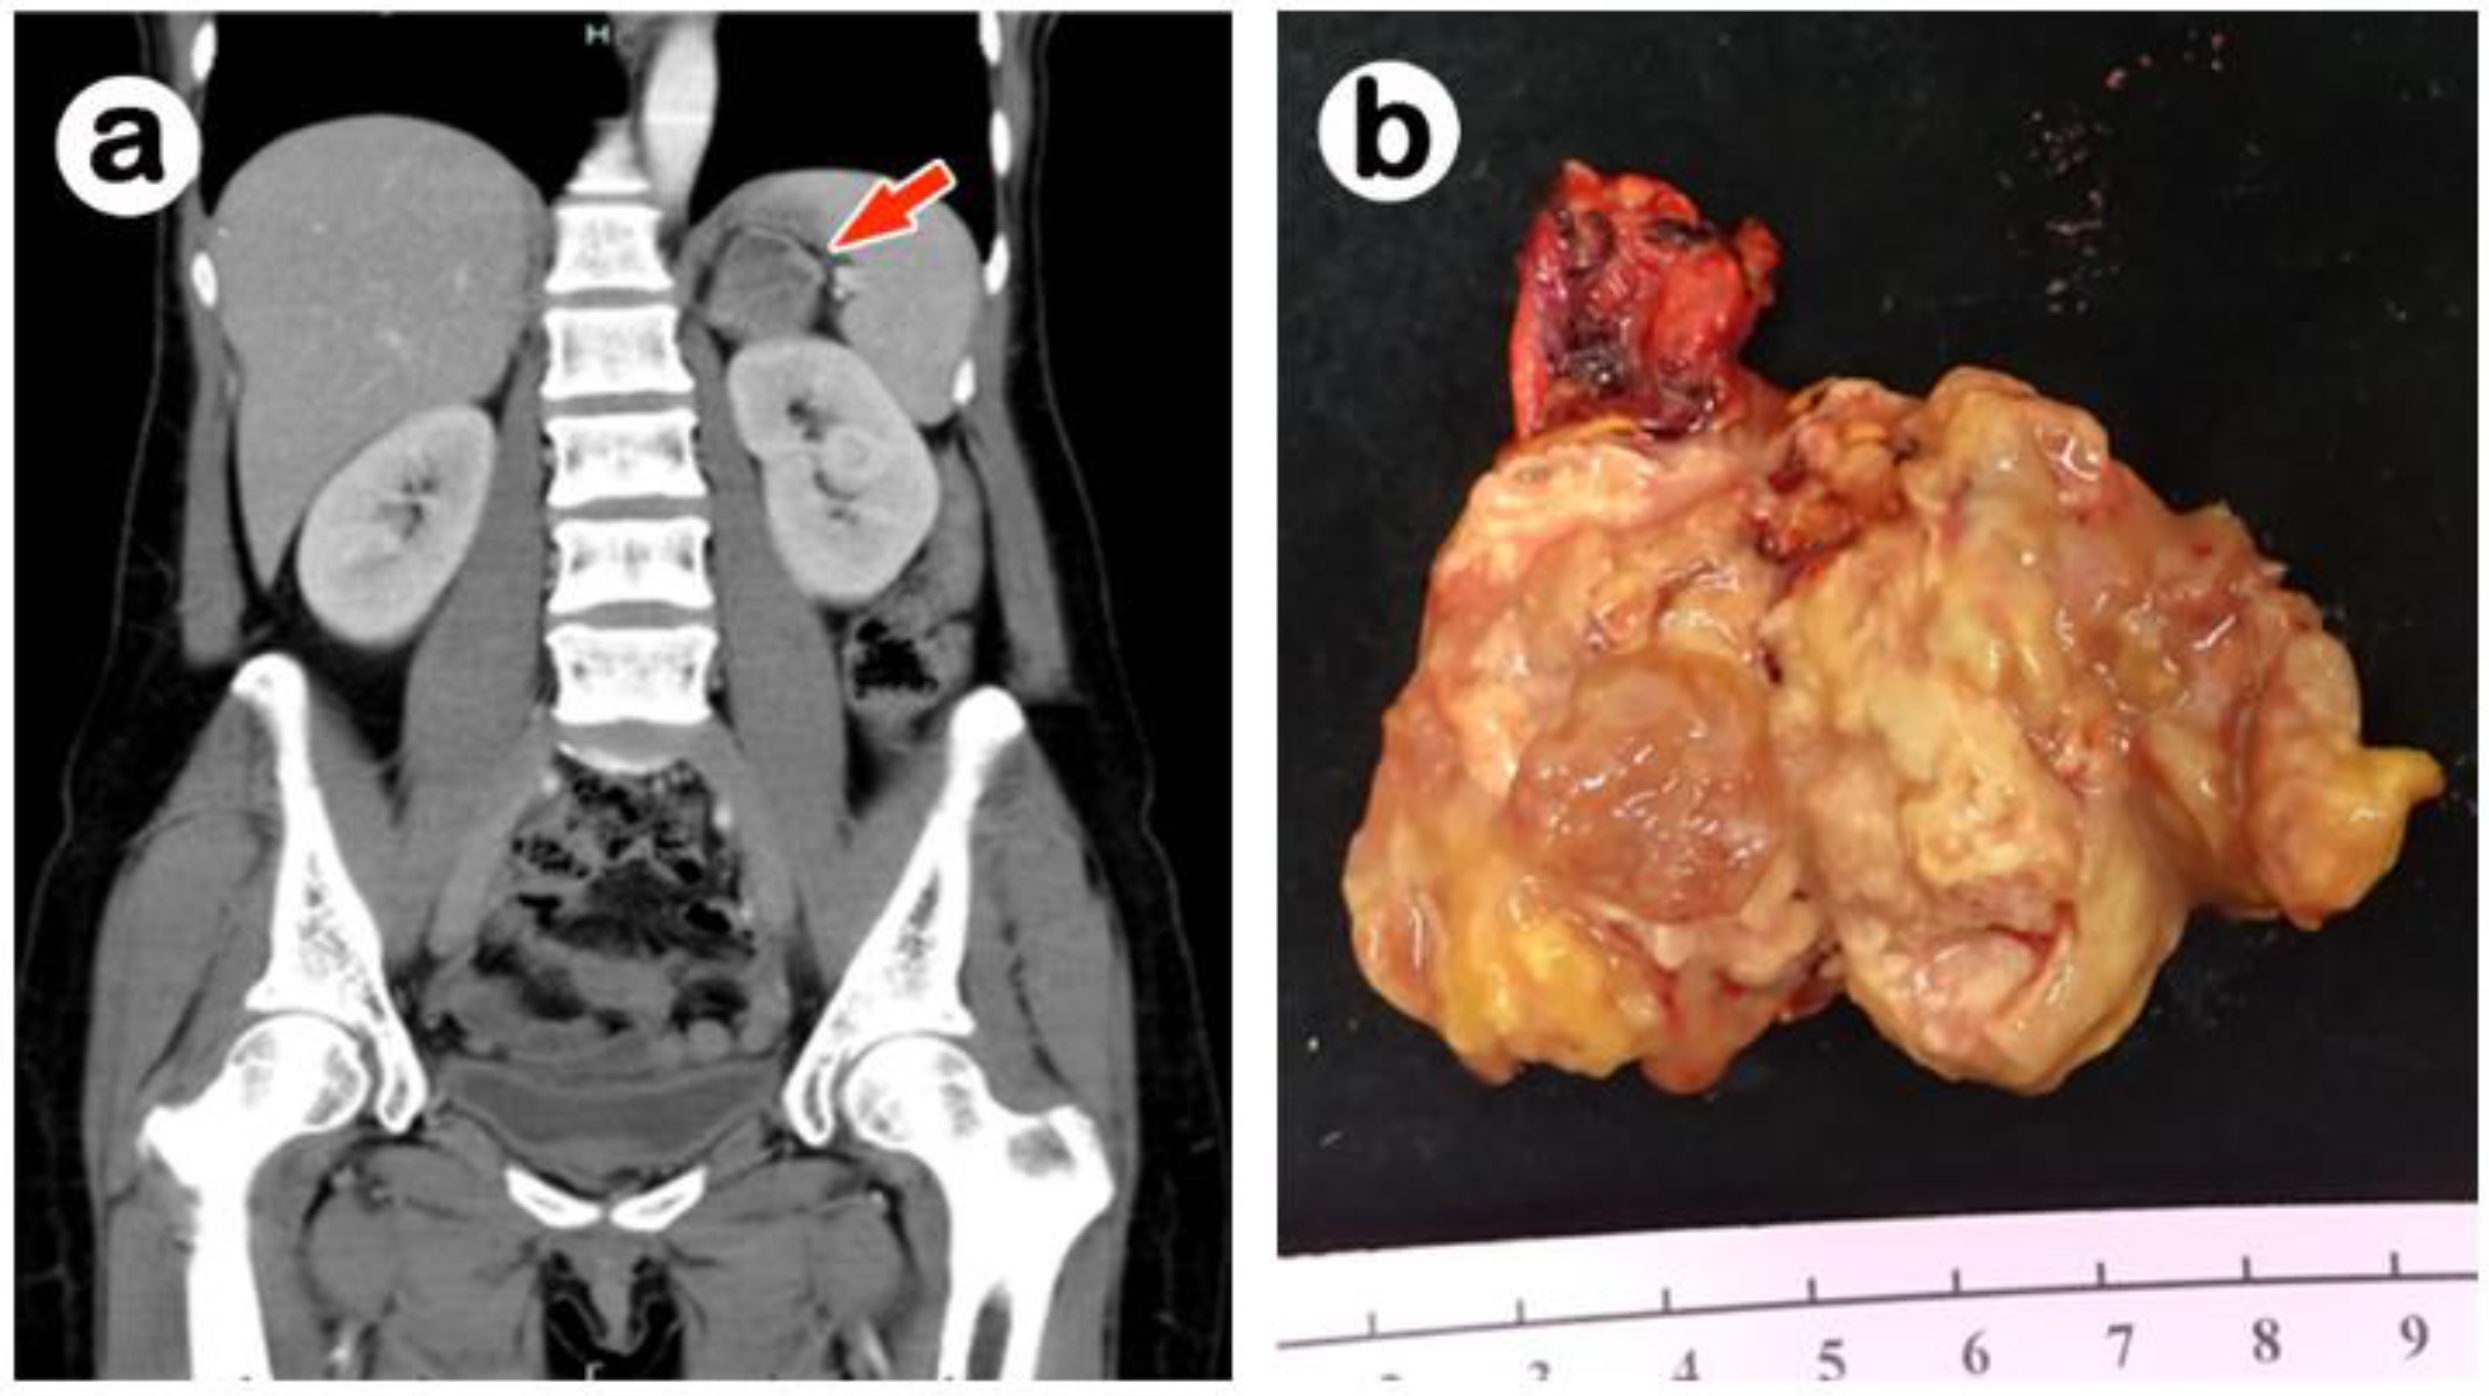

2. Case Report